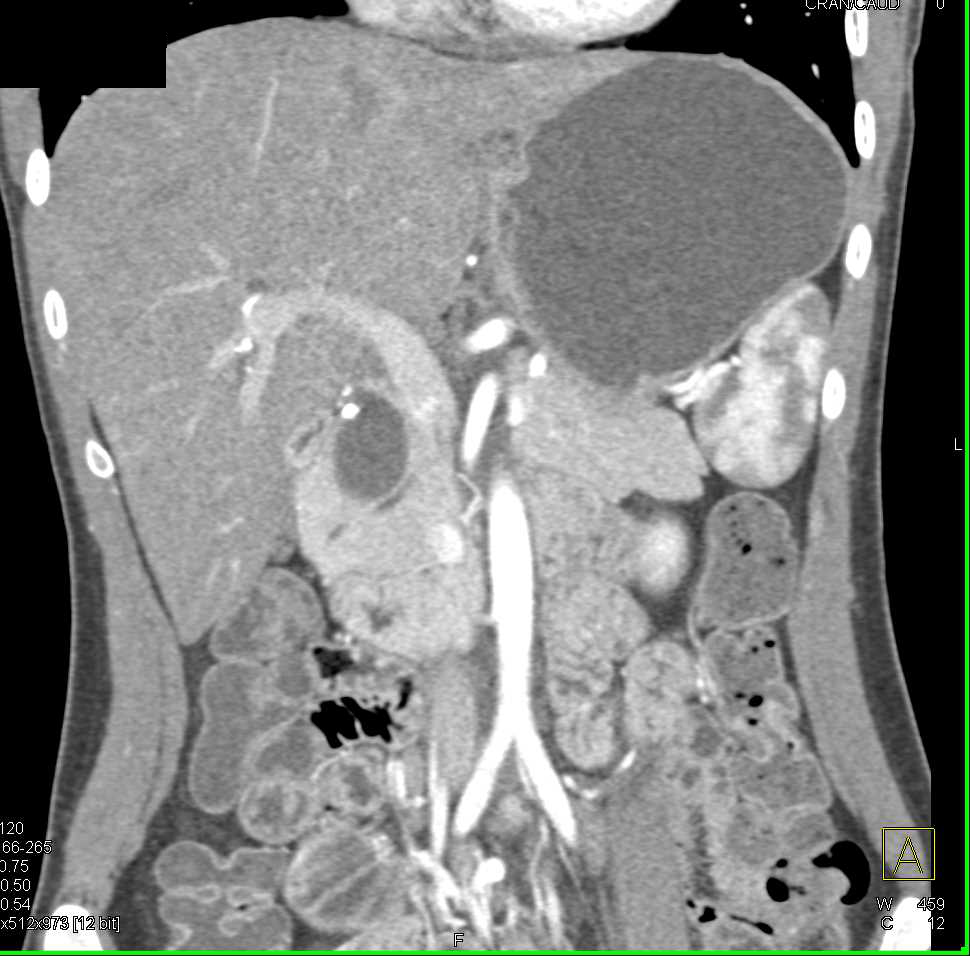

Cholangiocarcinoma with Left Ductal Dilatation and Atrophy of Left Lobe